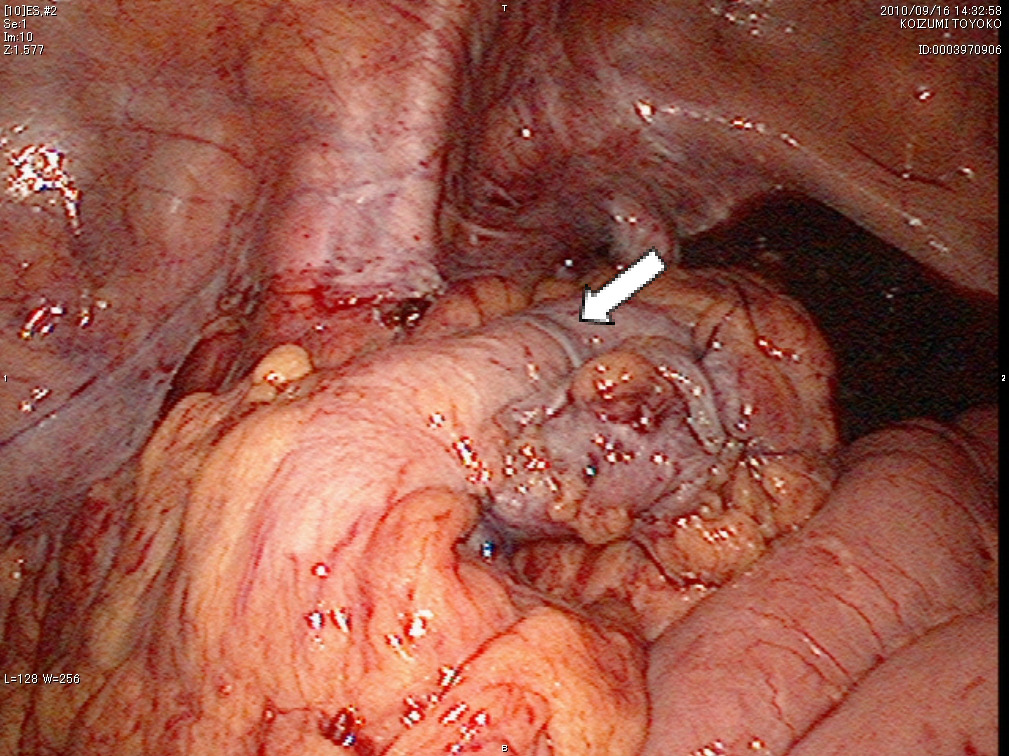

- 結腸がんの手術

結腸がんの手術では、がん病巣と周囲のリンパ節を同時に切除するために、がんの部位から10cmほど離れた腸管を切除し、断端をつなぎ合わせます。がんの存在部位により、回盲部切除術、右半結腸切除術、横行結腸切除術、左半結腸切除術、S状結腸切除術などの方法があります。がんを切除できない場合には、便の迂回路をつくるバイパス術やお腹に人工肛門(ストマ)をつくる手術を行うことがあります。 - 直腸がんの手術

以前は開腹手術が行われていましたが、現在では小さな手術創で体にやさしい腹腔鏡下手術やロボット支援下手術が主に行われるようになりました。これらの手術法により出血量の少ない精密な手術が可能になりました。美容的に優れているだけでなく、術後早期から食事が開始でき、早く退院できる(術後7~14日)ことや術後の腸閉塞が起こりにくいことなどの利点があります。

腹腔鏡下S状結腸切除術の術野

b)腸管吻合後状態(⇩)